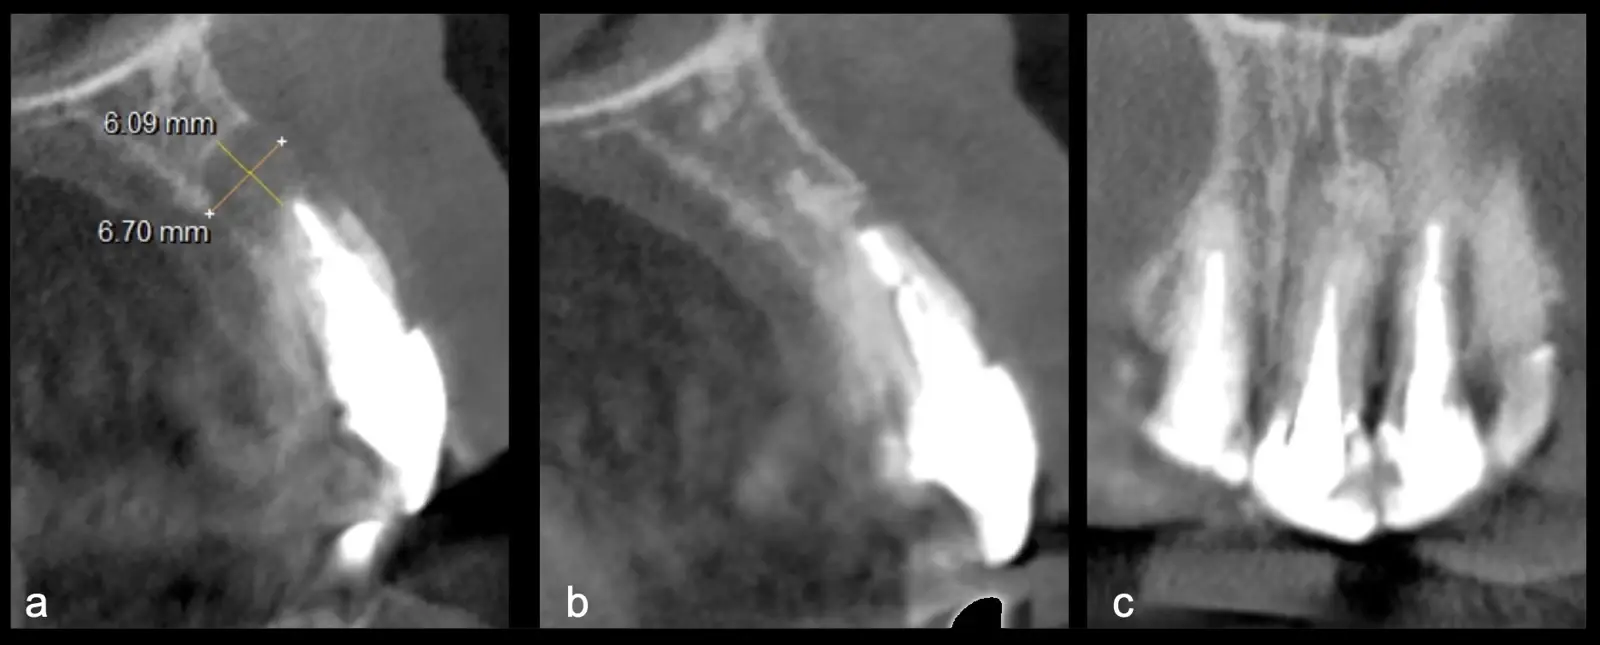

La microcirugía endodóntica apical busca conservar la mayor cantidad de longitud de raíz y de hueso circundante sano para no afectar la estabilidad de la pieza.11 Por ello, es ideal el uso de microscopios, elementos de magnificación, instrumental específico (insertos de ultrasonido endodónticos) y materiales de sellado eficientes para el tratamiento retrogrado. Su éxito es alto y evidencia una cicatrización ósea completa en el 74% de los casos al año de tratamiento.12 Cabe destacar que este logro está asociado también, a predictores propios de cada paciente, como la edad, tipo de pieza, profundidad de sondaje y extensión de la lesión.1 El uso complementario de la tomografía computarizada es resaltante como el instrumento imagenológico de elección para la etapa de planificación microquirúrgica,13 ya sea para una ejecución a mano alzada o con guías prefabricadas.14,15

El origen puede ser bacteriano (colonias bacterianas persistentes4, patología periodontal asociada5, reinfecciones por falta de sellado coronal), mecánico (preparación deficiente, fractura de instrumentos, fracturas radiculares6, extravasación de material de obturación7 con ó sin compromiso de estructuras vecinas) y anatómico (conductos accesorios poco permeables o calcificados)8 (Figuras 1 - 4).